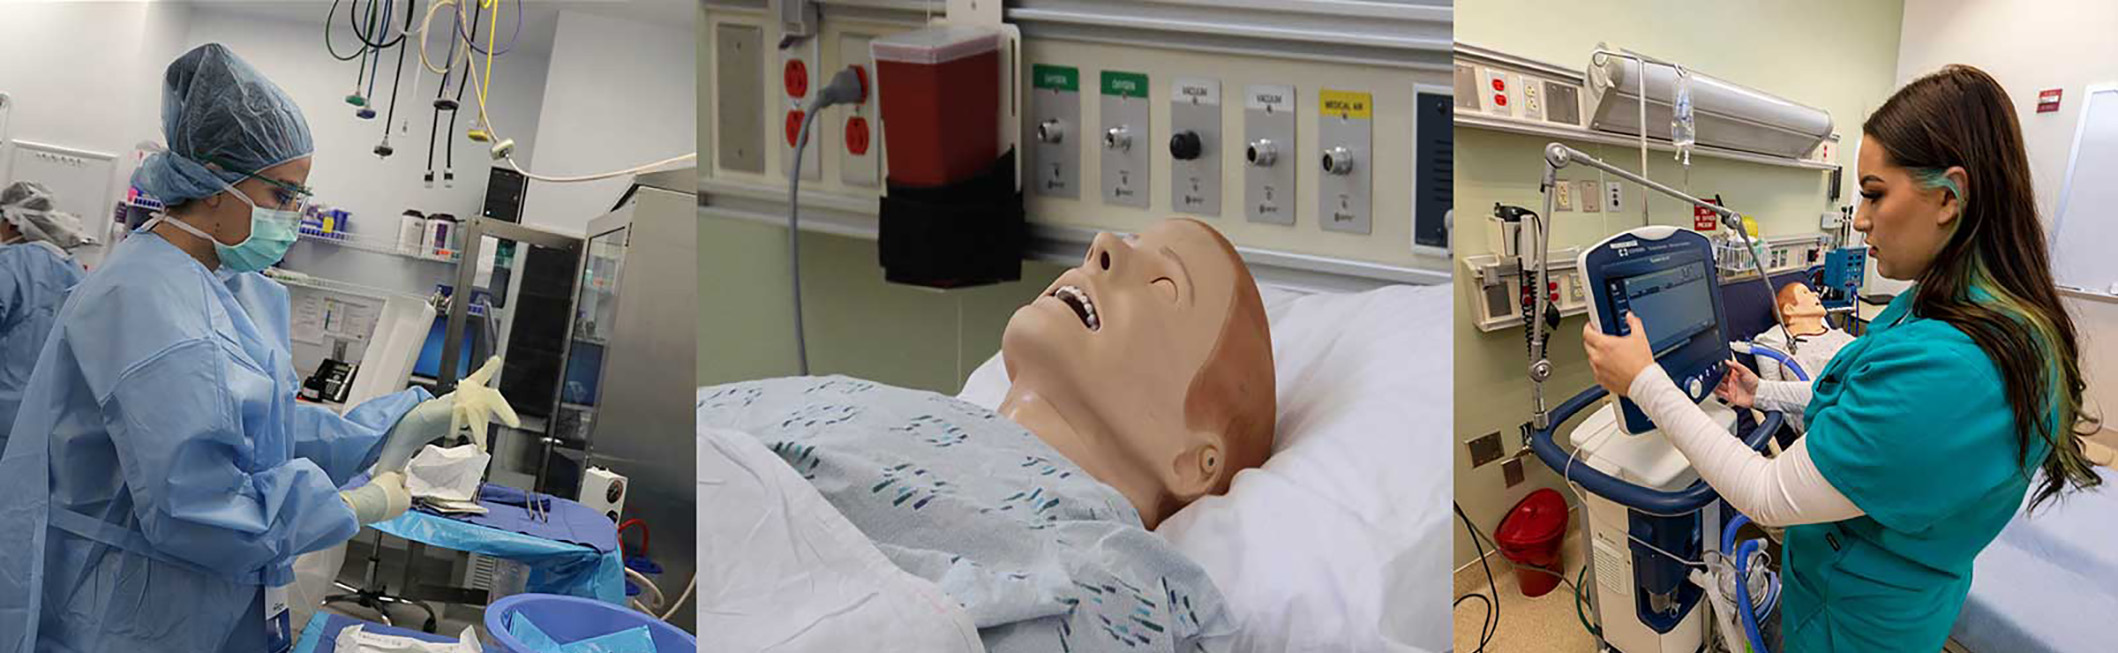

An Immersive Learning Experience

As a health science student, you'll gain hands-on experience in our Health Sciences Simulation Center. This simulation laboratory helps you build the skills you need to provide quality care. Our instructors will provide you with in-depth instruction in each simulation. In addition, each room is equipped with cameras, microphones, and monitors so instructors can debrief you and suggest improvements.

Facilities:

- Emergency room

- Intensive care unit

- Nurses station

- Labor and delivery unit

- Simulation lab and control room

- Adult, pediatric, and neonatal patient simulators